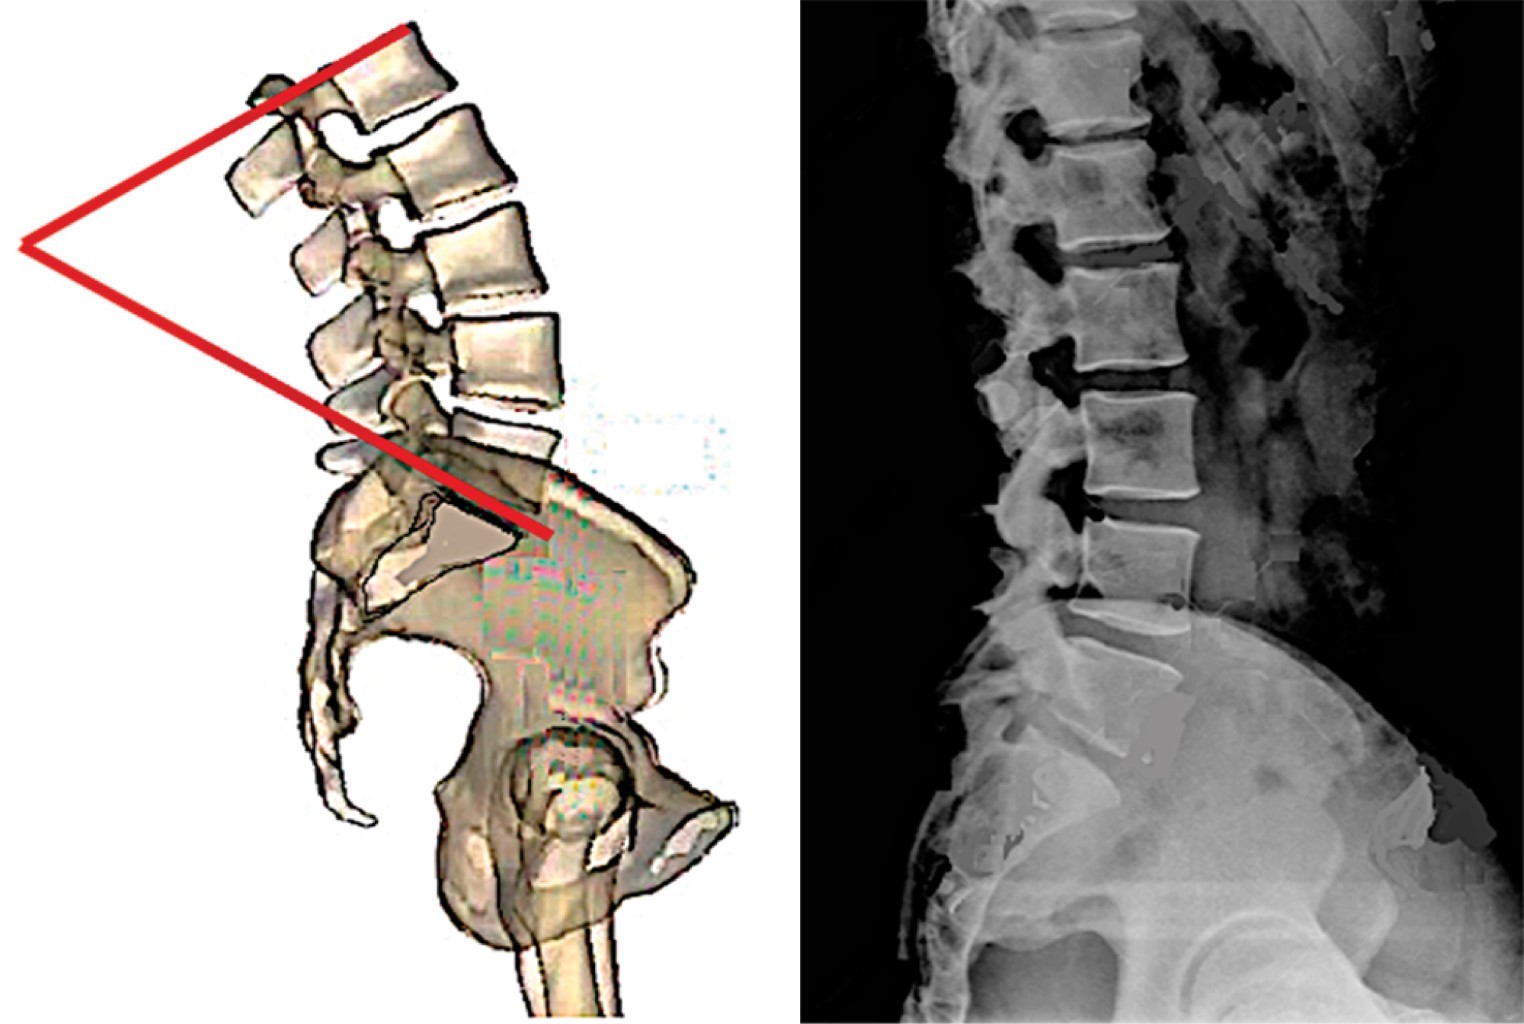

Pendiente sacra (ángulo de Ferguson). Es el ángulo que se forma entre el eje transversal y una línea paralela a la plataforma sacra. Un sacro verticalizado tiene un ángulo con valor bajo, un sacro horizontalizado tiene un valor alto (Figura 12). Los valores promedio en mexicanos sanos son de 35.6° ± 7.8° en bipedestación y de 36.5° ± 7.9° en decúbito.33

El ángulo de pendiente sacra permite determinar la magnitud de la lordosis lumbar ya que éste determina la magnitud de su curvatura; es decir, a menor pendiente, menor lordosis y a mayor pendiente mayor lordosis. Observe en la Figura 13 los efectos de la pendiente sacra en la magnitud de la lordosis lumbar.

Figura 13